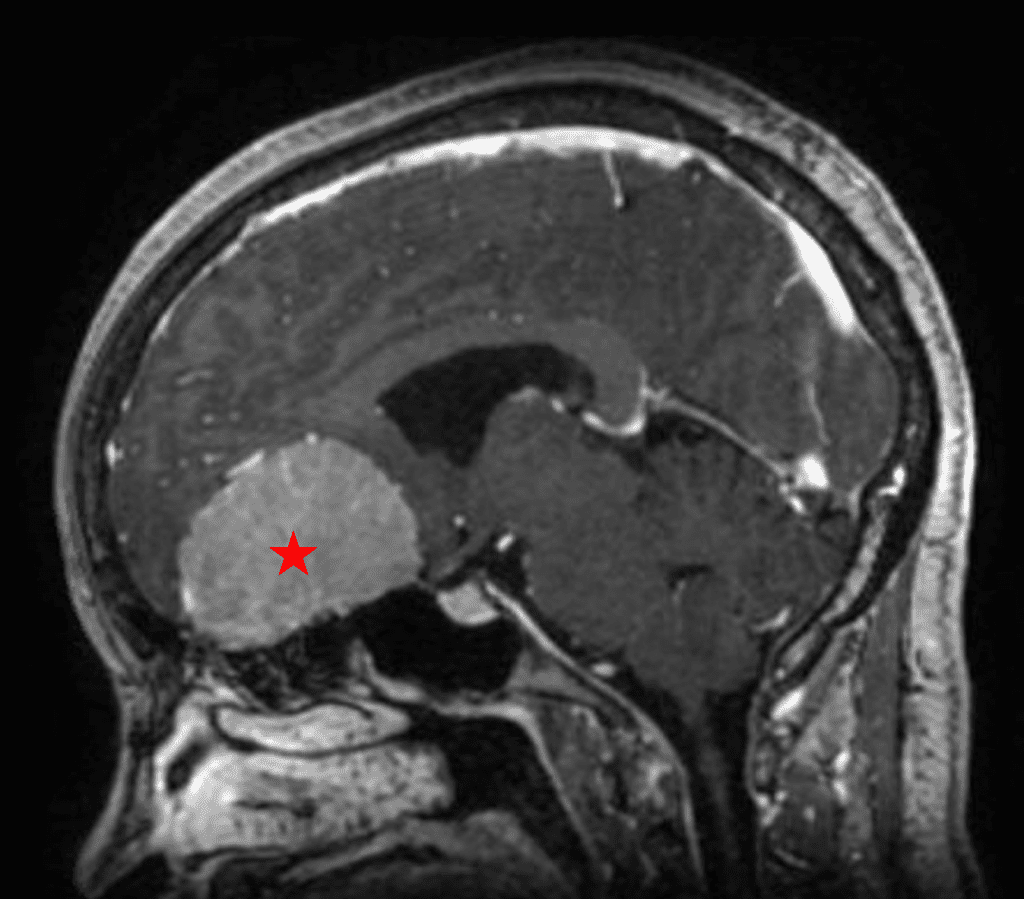

She was started on high-dose steroid and antiseizure prophylactic medicine. Surgical intervention was offered for mass effect, symptomatic relief, neurologic preservation, and histopathologic diagnosis. Dr. Gaudin performed a bifrontal craniotomy with complete resection of neoplasm through an interhemispheric and subfrontal approach. Postoperative imaging demonstrated a gross total resection without residual tumor and resolution of mass effect (Figure 1b and 2b). Intraoperative pathology was consistent with meningioma, WHO grade 1. She recovered very well, and was discharged home on postoperative day 3. On her follow-up outpatient visit, her preoperative symptoms had fully resolved, and her olfactory sense was maintained.

Figure 2a – Preoperative MRI demonstrating an extra-axial lesion with surrounding vasogenic edema and mass effect on the frontal lobes.

Figure 2b – Postoperative MRI demonstrating resolution of mass effect.